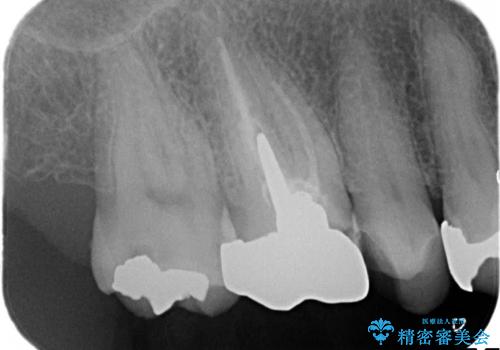

神経の無い歯のクラウン(かぶせ物)は、根管治療を顕微鏡下でしっかりとやり直し、その後に土台の築造とかぶせ物の製作を行うことで今後問題が生じる可能性を可及的に低くできます。

- 神経のある歯を先にセラミック修復し、その後根管治療のやり直しを行う

- 根管治療により痛みや腫れがひかない事や、術後に痛みや腫れが生じる事、治療によるファイル破折やパーフォレーションなどの偶発症、術後の歯根破折を生じる可能性もあります